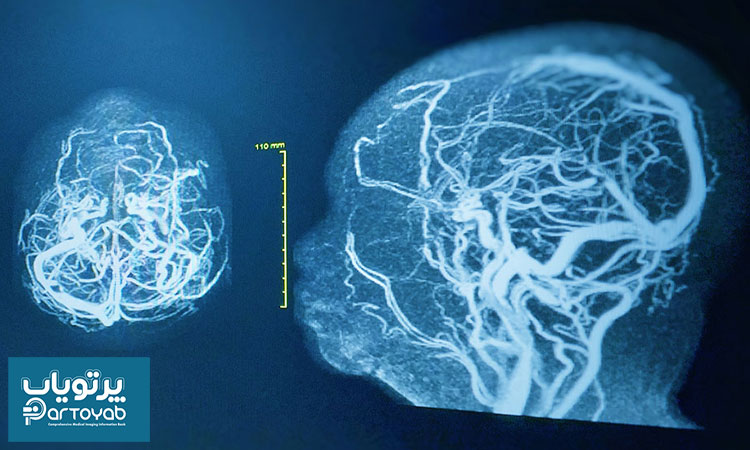

دوشنبه 16 مهر 1403

در این مطلب از سایت پرتویاب به بررسی اقدامات بعد از آنژیوگرافی مغز برای شما عزیزان خواهیم پرداخت. با ما همراه باشید.